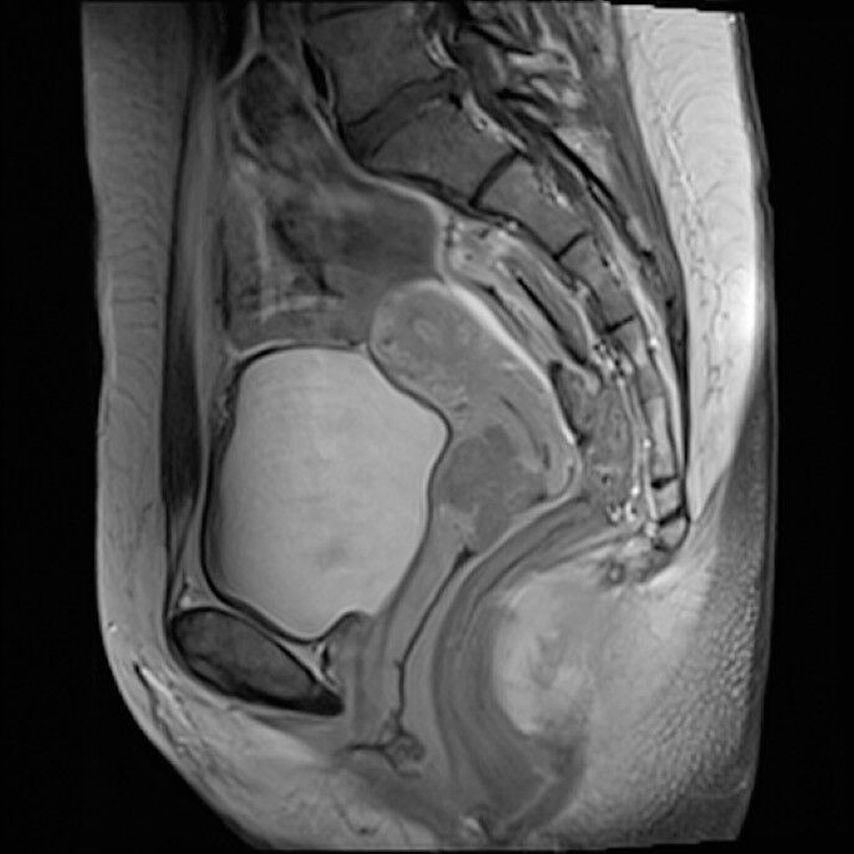

Radiochemotherapie

Patient:innen mit nodal-positiven bzw. lokal fortgeschrittenen Zervixkarzinomen werden mit Radiochemotherapie bestehend aus einer Beckenbestrahlung, einer „image-guided“ Brachytherapie und einer wöchentlichen Chemotherapie mit Cisplatin als Radiosensitizer therapiert. Die EMBRACE-Studie8 zeigte mit moderner, MR-basierter Brachytherapie eine lokale Tumorkontrollrate von ca. 90%. Diskutiert wird die Rolle einer neoadjuvanten Chemotherapie vor der definitiven Radiochemotherapie.9